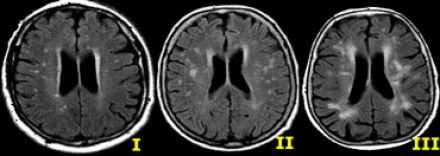

圖片六:白質(zhì)病變,F(xiàn)azekas分級為I、II 、III級

衰老過程出現(xiàn)白質(zhì)變化的臨床意義尚未完全闡明。多個腦血管危險因素與白質(zhì)病變有關(guān),除高血壓之外,其中最強的危險因素就是衰老。是否是生理性的白質(zhì)變化,取決于患者的年齡。

根據(jù)Fazekas評分量表,可將白質(zhì)變化分為不同的程度:

1. 輕度:點狀白質(zhì)損傷病灶,F(xiàn)azekas分級為I級。

2. 中度:融合的白質(zhì)損傷病灶,F(xiàn)azekas分級為II 級,在深部白質(zhì)中出現(xiàn)這種病灶可以認為是衰老過程中的正常生理性改變。

3. 重度:廣泛融合的白質(zhì)損傷病灶,F(xiàn)azekas分級III級,這種改變是病理性的。